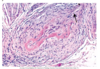

The provided image is an example of what pathology?

Prominent features of this pathology?

Acute Fibrinous Viral Pericarditis (type of pericarditis isn’t as important)

- Shaggy appearance (white arrows) of thickened pericardium due to fibrin deposition

- Extensive deposits of fibrin (black curved arrow) on the surface adn scant vascular proliferation (open arrow, center)